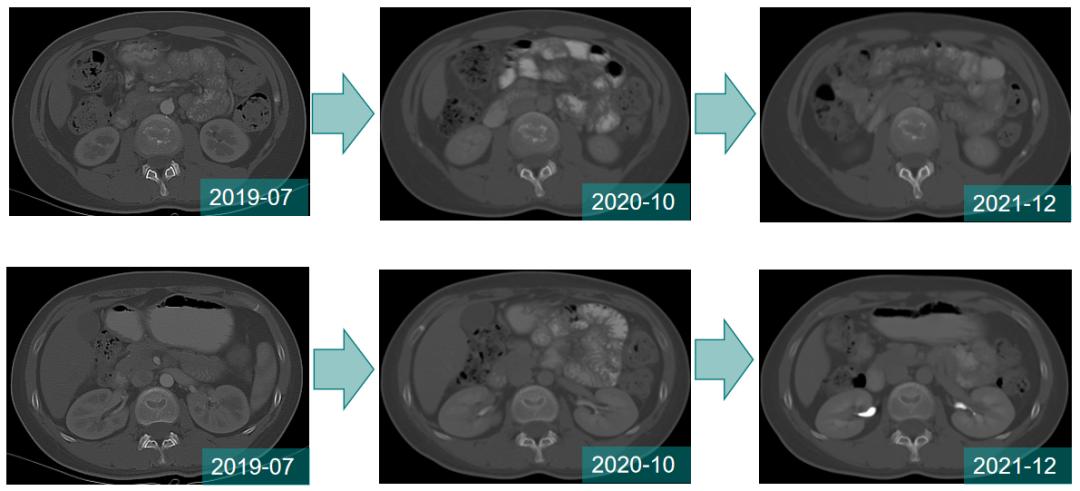

2周期治疗后腰骶部疼痛明显缓解;治疗期间每2周期评估疗效SD。

至今,骨转移病灶稳定,未出现新发病灶。